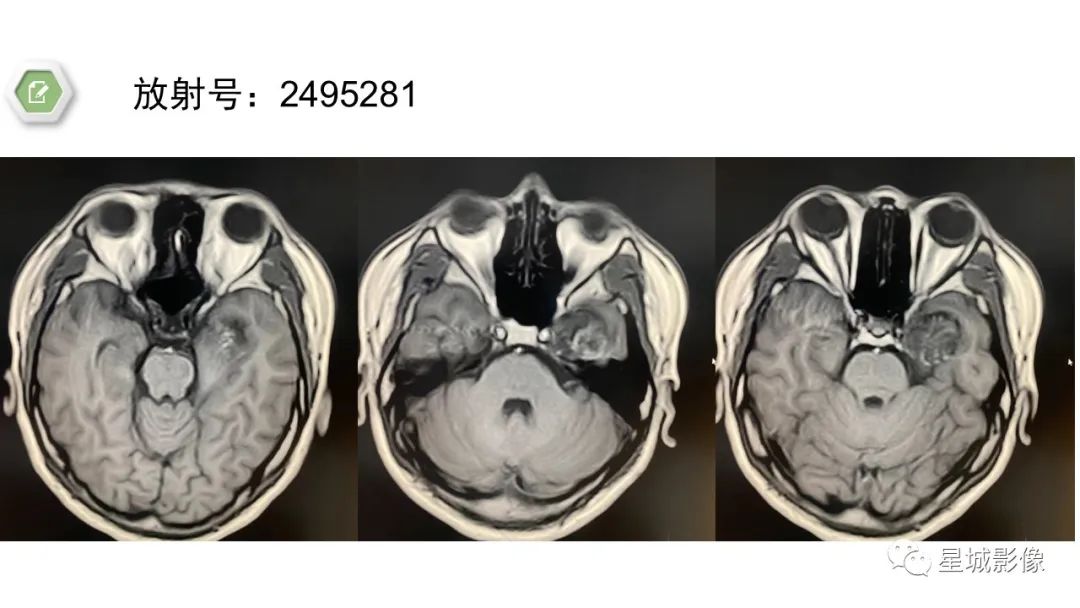

【病例】颅内成熟性囊性畸胎瘤1例MR影像表现-3